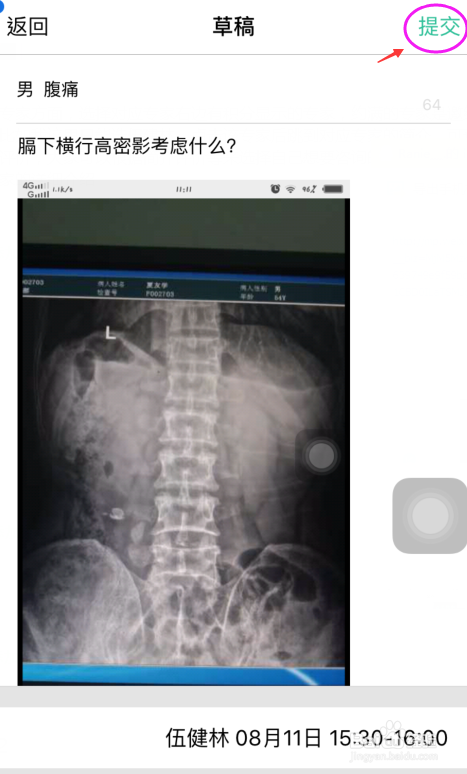

3、填写好咨询帖子的标题跟具体咨询的内容,配上病例图片以便专家可以通过图片更好给予咨询解答,咨询的内容尽量详细,内容填好后点击最下方的邀请值班专家